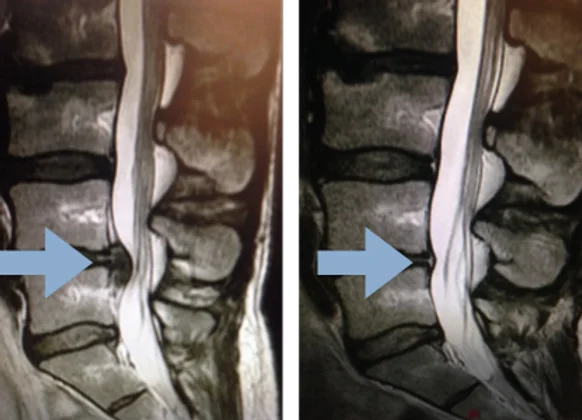

Carla was anxious as she waited for her second MRI results. Twelve weeks earlier, her first scan revealed a severe disc herniation at L5 putting direct pressure on the nerve, the source of her debilitating sciatica pain shooting down her leg.

When we reviewed her new MRI results, it was remarkable—her disc herniation had completely disappeared. There was no evidence it had ever existed, achieved without surgery.